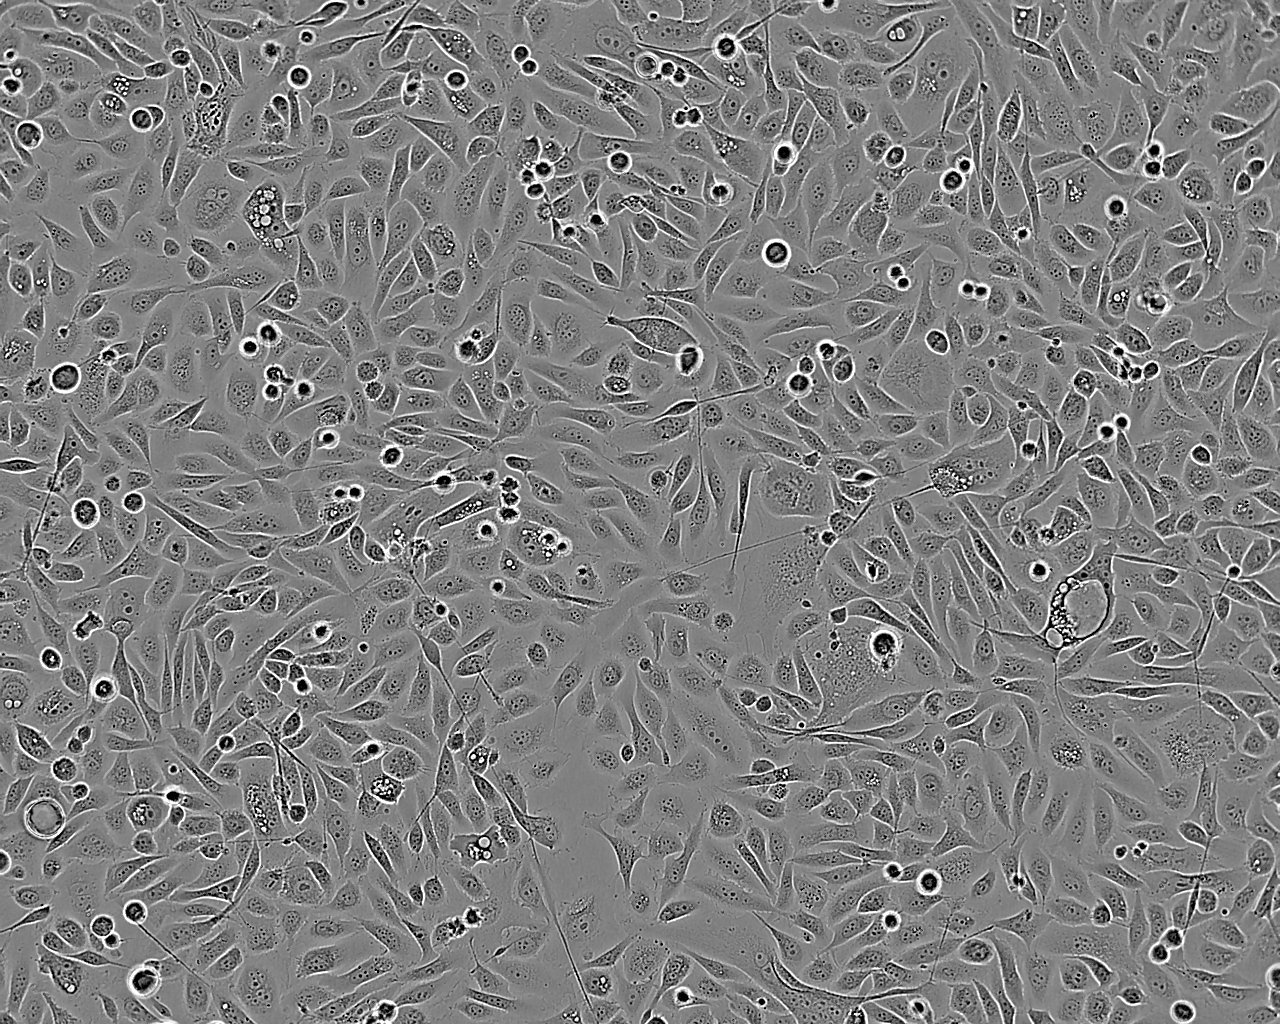

• PSN1细胞:人胰腺癌细胞系

PSN1细胞:人胰腺癌细胞系

细胞形态:上皮细胞样

细胞生长:贴壁

细胞生长特性:贴壁生长